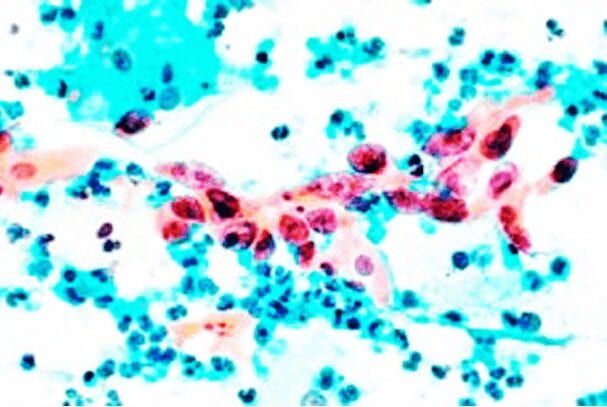

A New Method For Cervical Cancer Screening

At present, women over 30 years old are recommended to schedule cervical cancer screening every three years. In most countries, the gold standard for cervical cancer detection includes Pap smear and HPV tests. Women with an abnormal Pap test and and HPV positive test are referred for a colposcopy-driven biopsy. While a majority of these tests come back negative, biopsies are regularly administered. The current process is often emotionally taxing for women and creates unnecessary health costs.

LifeGene’s precision methylation kits will revolutionize cervical cancer screening. We are developing a non-invasive, streamlined solution for cervical cancer screening and prevention that uses a panel of precision epigenetic markers to identify aggressive cervical disease before a colposcopy-driven biopsy is prescribed. The result? Better prevention, at a lower cost.

Our CervicalMethDX Test is a precision methylation solution that triages HPV positive patients into colposcopy, biopsy or excision procedures.